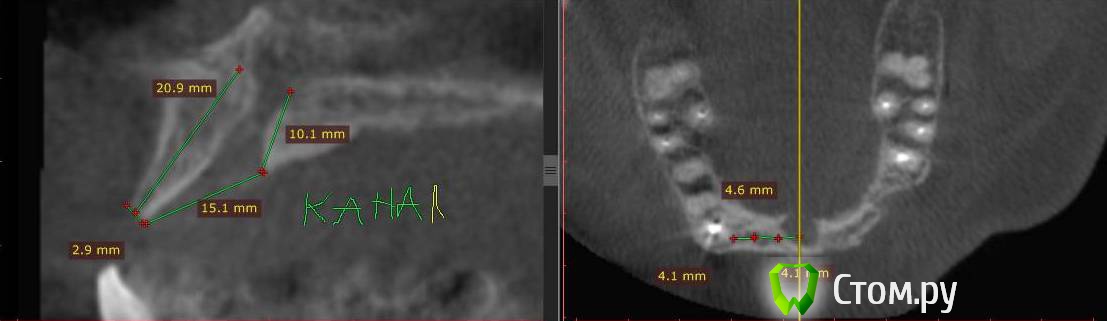

Togha Опубликовано 5 мая, 2014 Поделиться Опубликовано 5 мая, 2014 (изменено) Коллеги, обратился пациент, первый этап работы - устранение адентии между 14 и 23 зубами. По вертикали есть куда разбежаться (до анатомических образований от 17 и более мм), но вот гребень совсем узкий (от 2 до 5 мм), а также широкий резцовый канал (примерно 6.5 мм в диаметре). Между 14 и 23 расстояние 38 мм. Пациент решительно настроен на имплантацию. Хотел бы узнать, какую методику аугментации посоветуете, и как спозиционировать имплантаты? Склонялся к расщеплению гребня, нкр, имплантаты 3.75 мм на 10 мм, сделать мостик предлагает ортопед, на область 13, 11, 21, 22. Но как с расщеплением в зоне резцового канала и куда ставить имплантат 21 (как видно, есть значительное смещение канала от 11 в сторону 21), прямо в канал? Ссылка на DICOM файл http://yadi.sk/d/2vcbkBjaPBRgMСсылка на образ диска с просмотрщиком http://yadi.sk/d/csIsw0mYPBS2x На второй картинке примерно обозначен граница резцового отверстия вертикальными линиями Изменено 5 мая, 2014 пользователем Togha Ссылка на комментарий

Mane Опубликовано 6 мая, 2014 Поделиться Опубликовано 6 мая, 2014 Вы нарезали совсем ни то и ни так. Не разберешься на ваших срезах Ну никак. Нарежте и подпишите номер зуба. Нарежте зоны 13, 12, 22 Ссылка на комментарий